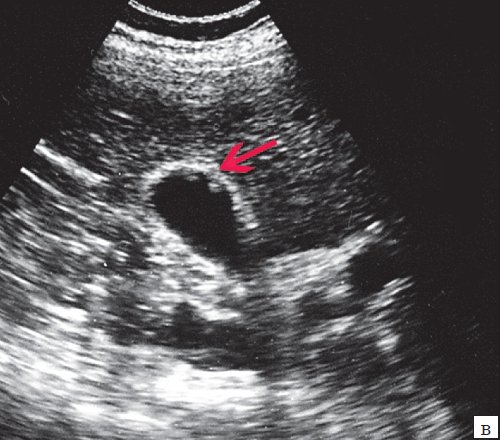

При УЗИ органов брюшной полости установлено: печень несколько увеличена в размерах, контуры ровные, четкие, структура неоднородная, повышенной эхогенности. Воротная вена 12 мм. Расширение внутрипеченочных протоков, долевые 5 мм, общий печеночный проток (ОПП) расширен до 20 мм, просвет представлен структурами по плотности мелких конкрементов, замазки, распространяющиеся на просвет правого долевого протока. Желчный пузырь размером 89x32 мм, стенка - 2 мм, в нем подобные массы. Общий желчный проток - 15 мм, просвет также представлен конкрементами и замазкой. Поджелудочная железа нормального размера, контуры ровные, структура диффузно неоднородная, повышенной эхогенности, проток не расширен. Селезенка нормального размера, средней эхогенности, селезеночная вена 7 мм. Заключение: конкременты желчного пузыря. Ультразвуковая картина низкого печеночного блока, обусловленного холедохолитиазом (рис. 7).

а) Увеличенный желчный пузырь (синяя стрелка), конкременты общего желчного протока (красная стрелка).

б) Множественные гиперэхогенные структуры в просвете общего желчного протока, с четкой теневой дорожкой.